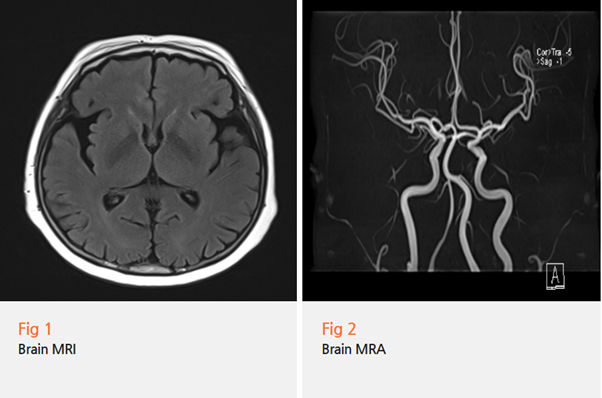

뇌 MRI는 뇌 조직 자체를 보는 검사입니다.

뇌의 구조, 뇌경색, 뇌출혈, 종양 등을 확인할 수 있어요.

마치 뇌를 얇게 썰어서 한 장 한 장 들여다보는 것처럼

세밀한 구조까지 파악할 수 있습니다.

그림10.png 촬영 일시: 2025.05.11

반면 MRA(자기공명혈관조영술)는 혈관을 보는 검사예요.

뇌혈관의 모양, 혈관 협착, 동맥류, 혈관 기형 등을 확인할 수 있죠.

혈관만 콕 찍어서 3D로 재구성해

보여주는 거라고 생각하시면 됩니다.

뇌혈관 MRA는 MRA의 한 종류로,

특히 뇌혈관에 특화된 검사라고 보시면 돼요.

쉽게 비유하면 이런 거예요.

뇌 MRI는 '집의 구조'를 보는 것이고,

뇌혈관 MRA는 '집 안의 수도관'을 보는 것이죠.

둘 다 중요하지만, 보는 포인트가 완전히 다른 거예요.

목 X-ray, 뇌 MRI, MRA 모두

뚜렷한 문제가 발견되지 않았어요.